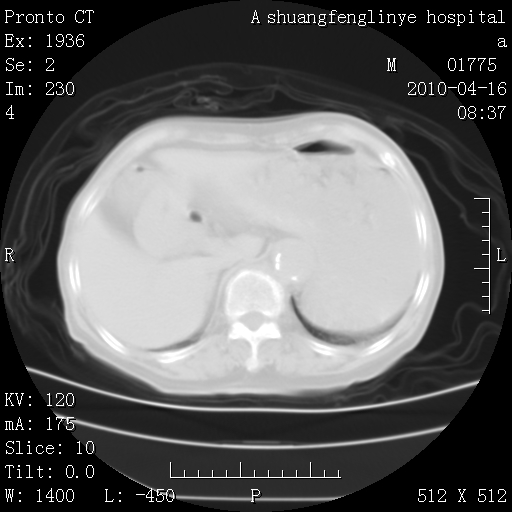

陈旧性结核,胃腔扩大,脾脏受压后移

慢支肺气肿,左上陈旧性结核,主动脉冠脉钙化

典型 夹层动脉瘤。 内膜瓣钙化移位

1)左肺上叶结核(纤维、增殖病灶)。2)冠状动脉及主动脉钙化。

1)左肺上叶结核(纤维、增殖病灶)。2)冠状动脉及主动脉钙化。肺动脉高压